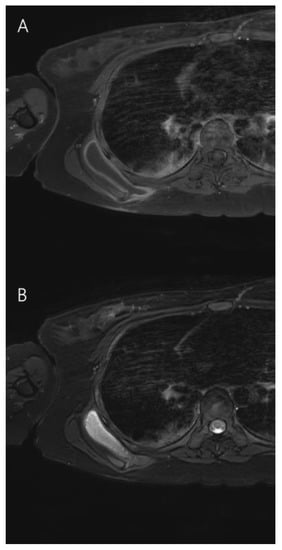

2. Case Presentation